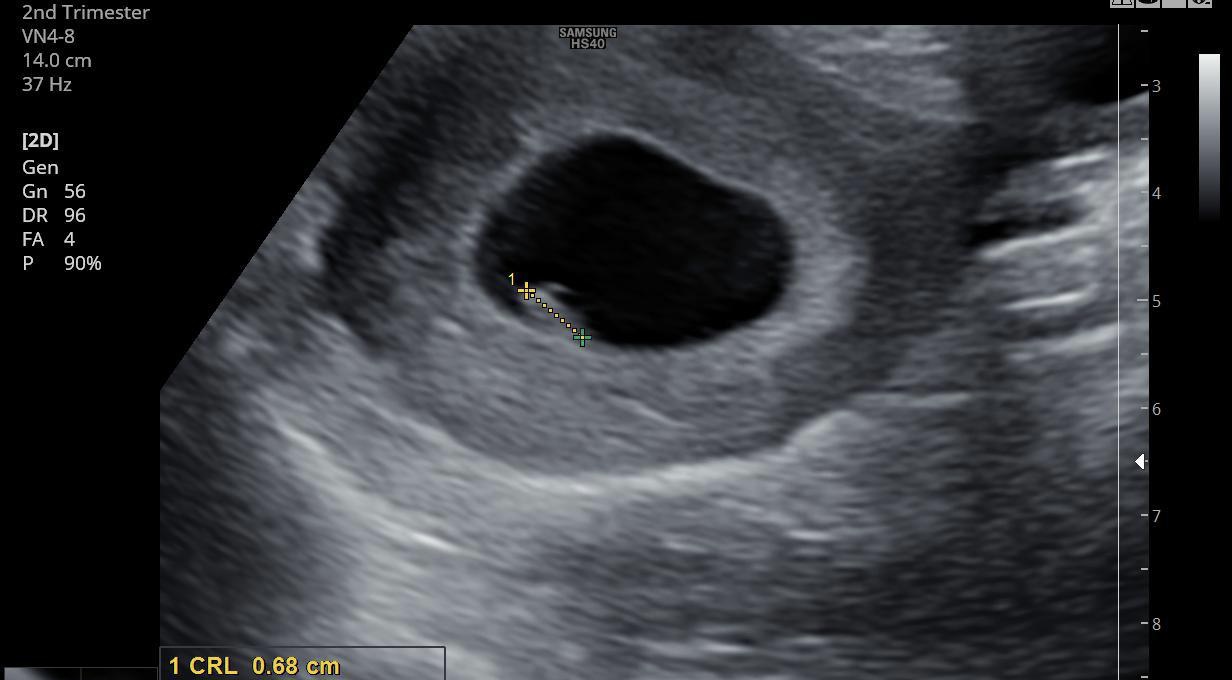

5 haftalıkken sağda üst köşede gözükmüştü. Ama Yeni gittm 7 haftalık olduk. karın ultrason görüntüleri bunlar rica etsem cinsiyet tahmininde bulunur musunuz? bu arada soldan yumurtlamışım

Ekli dosyalar

• D6A874AD-9FCB-405A-8B75-9CF3E5174581.jpeg

D6A874AD-9FCB-405A-8B75-9CF3E5174581.jpeg

169,4 KB · Görüntüleme: 209

• C2637F0F-CA8A-4868-8C21-156B562D137C.jpeg

C2637F0F-CA8A-4868-8C21-156B562D137C.jpeg

109,9 KB · Görüntüleme: 224

• 79659AC2-9C38-4FF8-8BEA-1421B734267C.jpeg

79659AC2-9C38-4FF8-8BEA-1421B734267C.jpeg

238,5 KB · Görüntüleme: 211